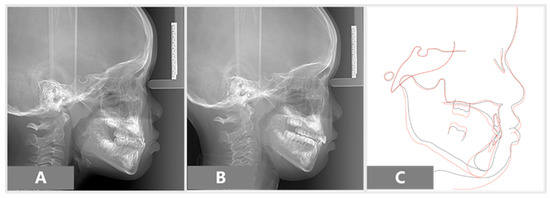

| Angular/Linear Measurement | Mean (6 Years) | Initial | Final |

|---|---|---|---|

| SNA (°) | 81–83 | 82 | 82 |

| SNB (°) | 79–81 | 82 | 79 |

| ANB (°) | 2–4 | 0 | 3 |

| Wits Appraisal (mm) | 0–1 | −4.5 | −4 |

| FMA (°) | 22–28 | 23.6 | 30 |

| IMPA (°) | 87–89 | 88 | 81 |

| U1 to NA (mm) | 21–23 | 15 | 24 |

| L1 to NB (mm) | 24–26 | 20 | 16 |

| NSAr (saddle angle) (°) | 118–126 | 128 | 128 |

| Gonial angle (°) | 129.8 | 146 | 135 |

| NSGn (°) | 59.8 | 67 | 67 |

| Y-axis (°) | 53–66 | 61 | 66 |

| Nasion perpendicular to point A (mm) | 0–1.0 | −2.7 | −3.6 |

| Upper pharyngeal space (mm) | 15–20 | 6.4 | 6 |

| Lower pharyngeal space (mm) | 11–14 | 12.7 | 11.8 |